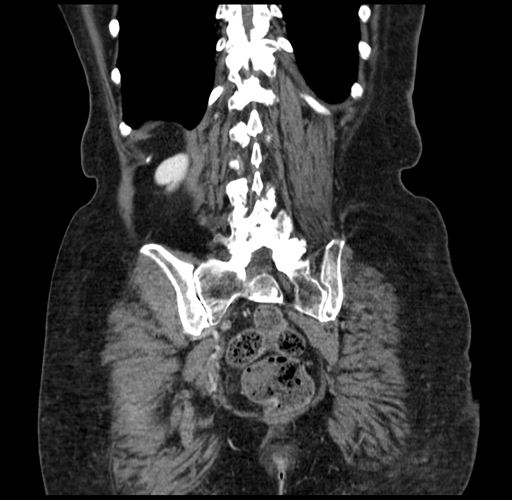

Pre-Chemo: Coronal Venous

Coronal Venous